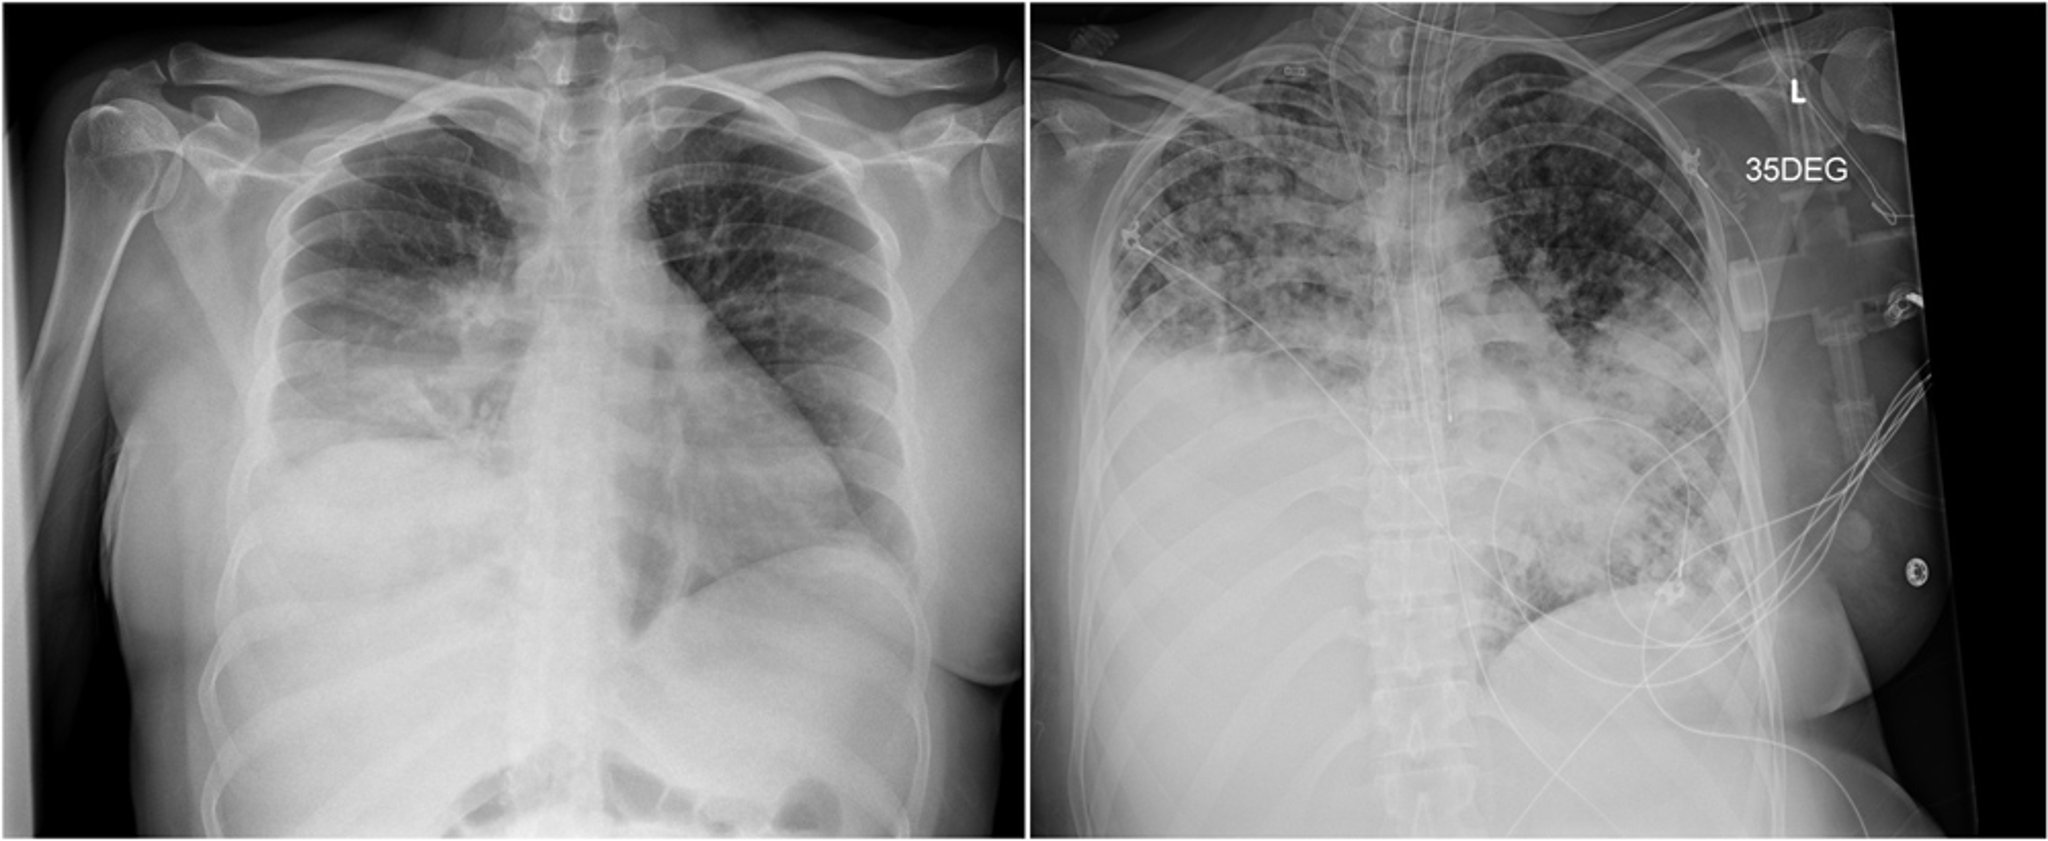

Das linke Röntgenbild zeigt eine Konsolidierung des rechten Unterlappens, die fälschlicherweise für eine bakterielle Pneumonie gehalten wurde. Die drei Wochen später angefertigte Röntgenaufnahme der rechten Seite zeigt ein Fortschreiten der Krankheit mit fleckigen bilateralen Luftraumtrübungen und einer dichten Konsolidierung im rechten Unterlappen.

Images courtesy of Paschalis Vergidis, MD, MSc.